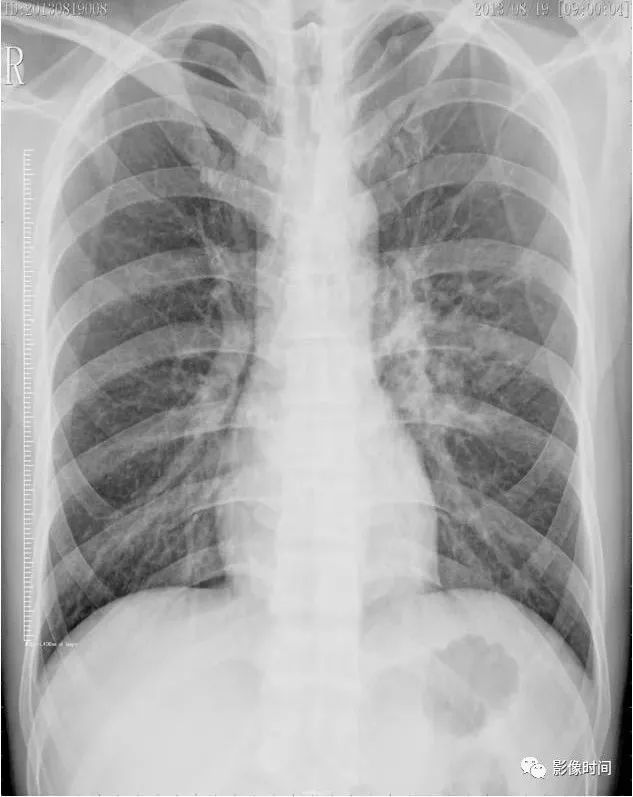

病例 1:同一小叶性肺炎患者于同日拍摄的胸片和肺 ct.

沿肺纹理有模糊的斑片状阴影.肺纹理增粗,模糊.x线表现

2.小叶性肺炎 表现为肺纹理增多,模糊.